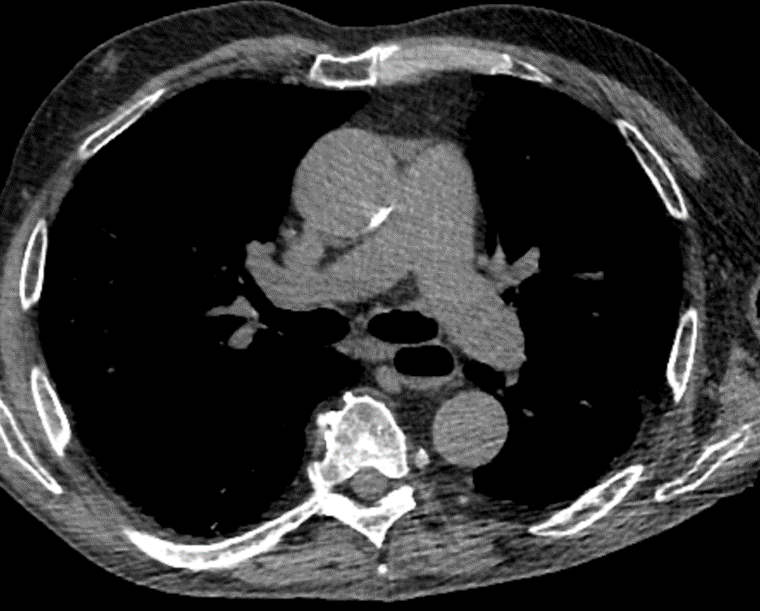

Coronary artery calcification

Coronary artery calcification can be identified as high-attenuation material in the path of a coronary artery. For non-gated thoracic CT in routine clinical practice, it is recommended to use a simple visual ordinal score performed on a whole-patient basis. CAC is scored as absent, mild, moderate, or severe on a whole-patient basis to summarize the cumulative findings in all the coronary arteries. This approach can be applied to both non-contrast and contrast-enhanced images.